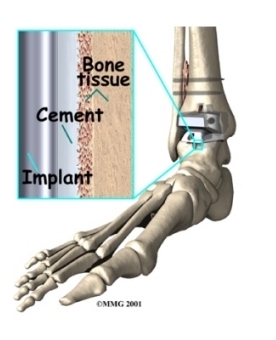

Your surgeon may use a special type of epoxy cement to attach the metal components to the bone. This is called a .